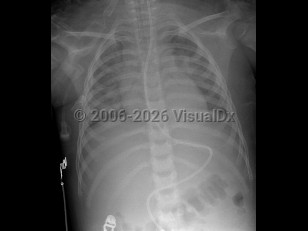

Imaging Studies image of Smoke inhalation - imageId=3014655. Click to open in gallery.  caption: 'Image from frontal chest x-ray in a child demonstrating bilateral, diffuse interstitial opacities, consistent with pulmonary edema. There is an endotracheal tube in the trachea, as well as an enteric tube extending into the duodenum.'

Image from frontal chest x-ray in a child demonstrating bilateral, diffuse interstitial opacities, consistent with pulmonary edema. There is an endotracheal tube in the trachea, as well as an enteric tube extending into the duodenum.